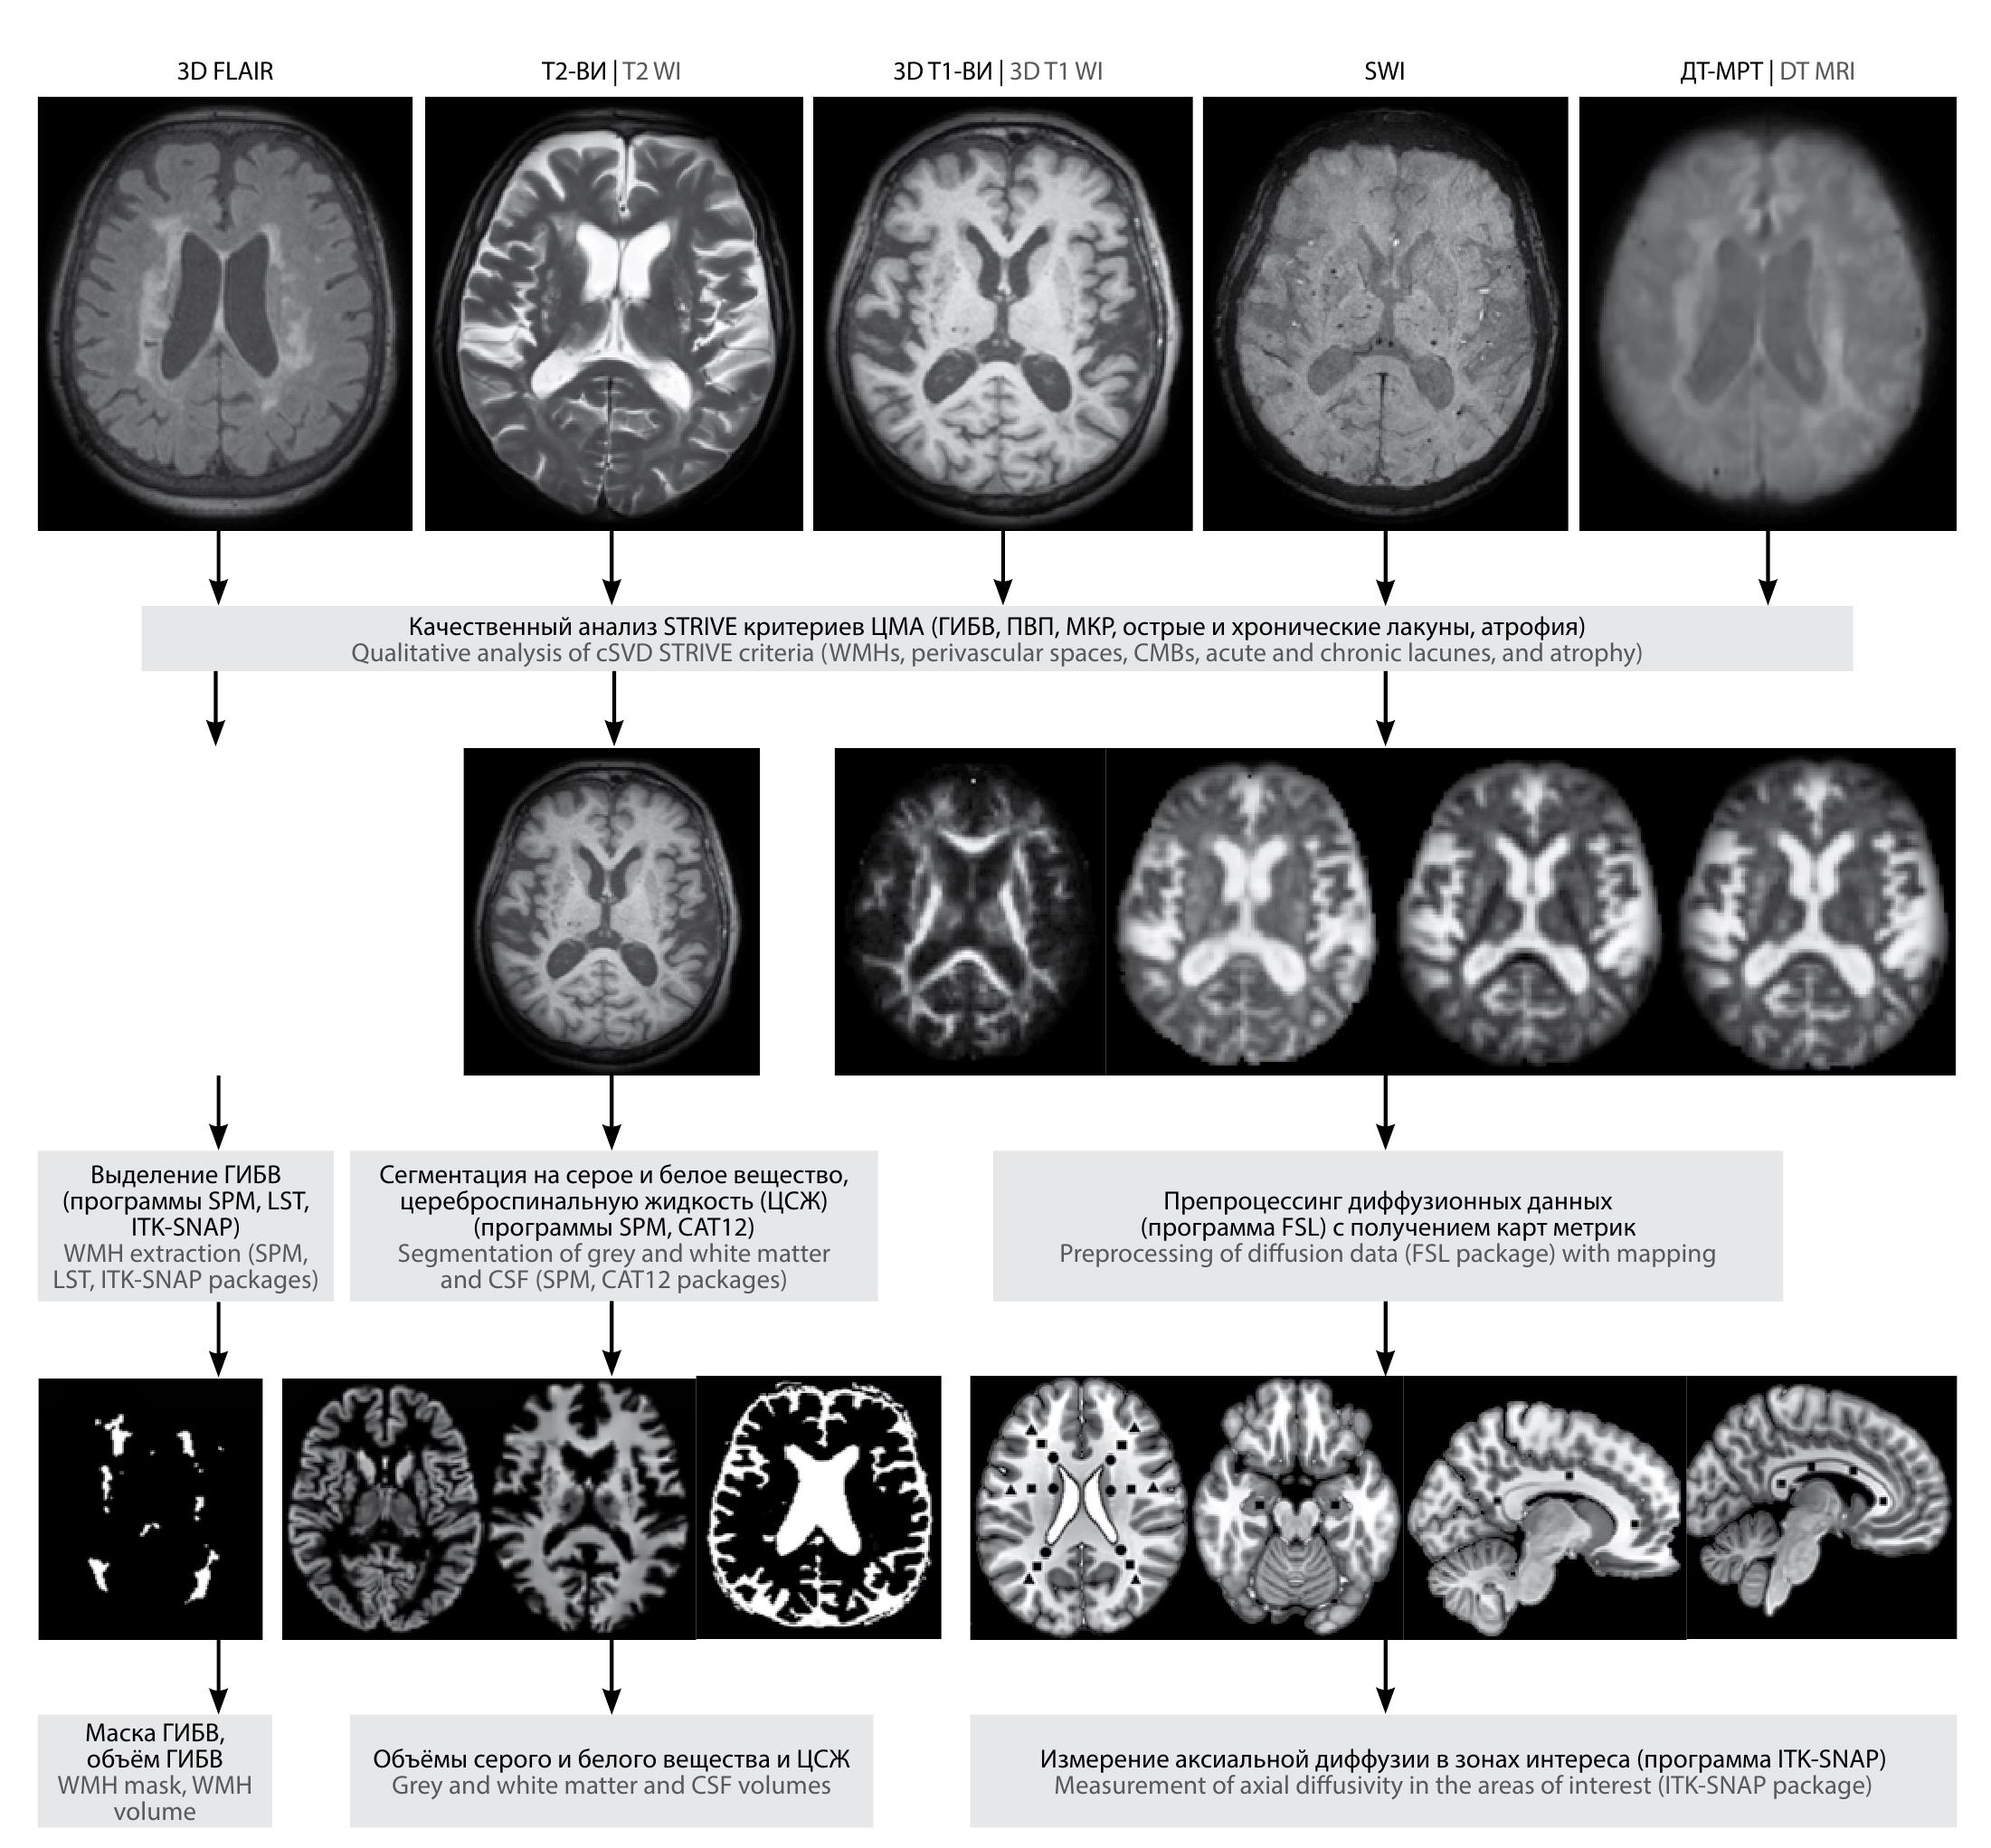

Условия проведения МРТ-исследований были аналогичны таковым в 2016–2017 гг. [29, 30]. Методы анализа изображений представлены на рис. 2.

Рис. 2. Алгоритм мультимодального МРТ-обследования.

Fig. 2. Multimodal MRI scanning algorithm.